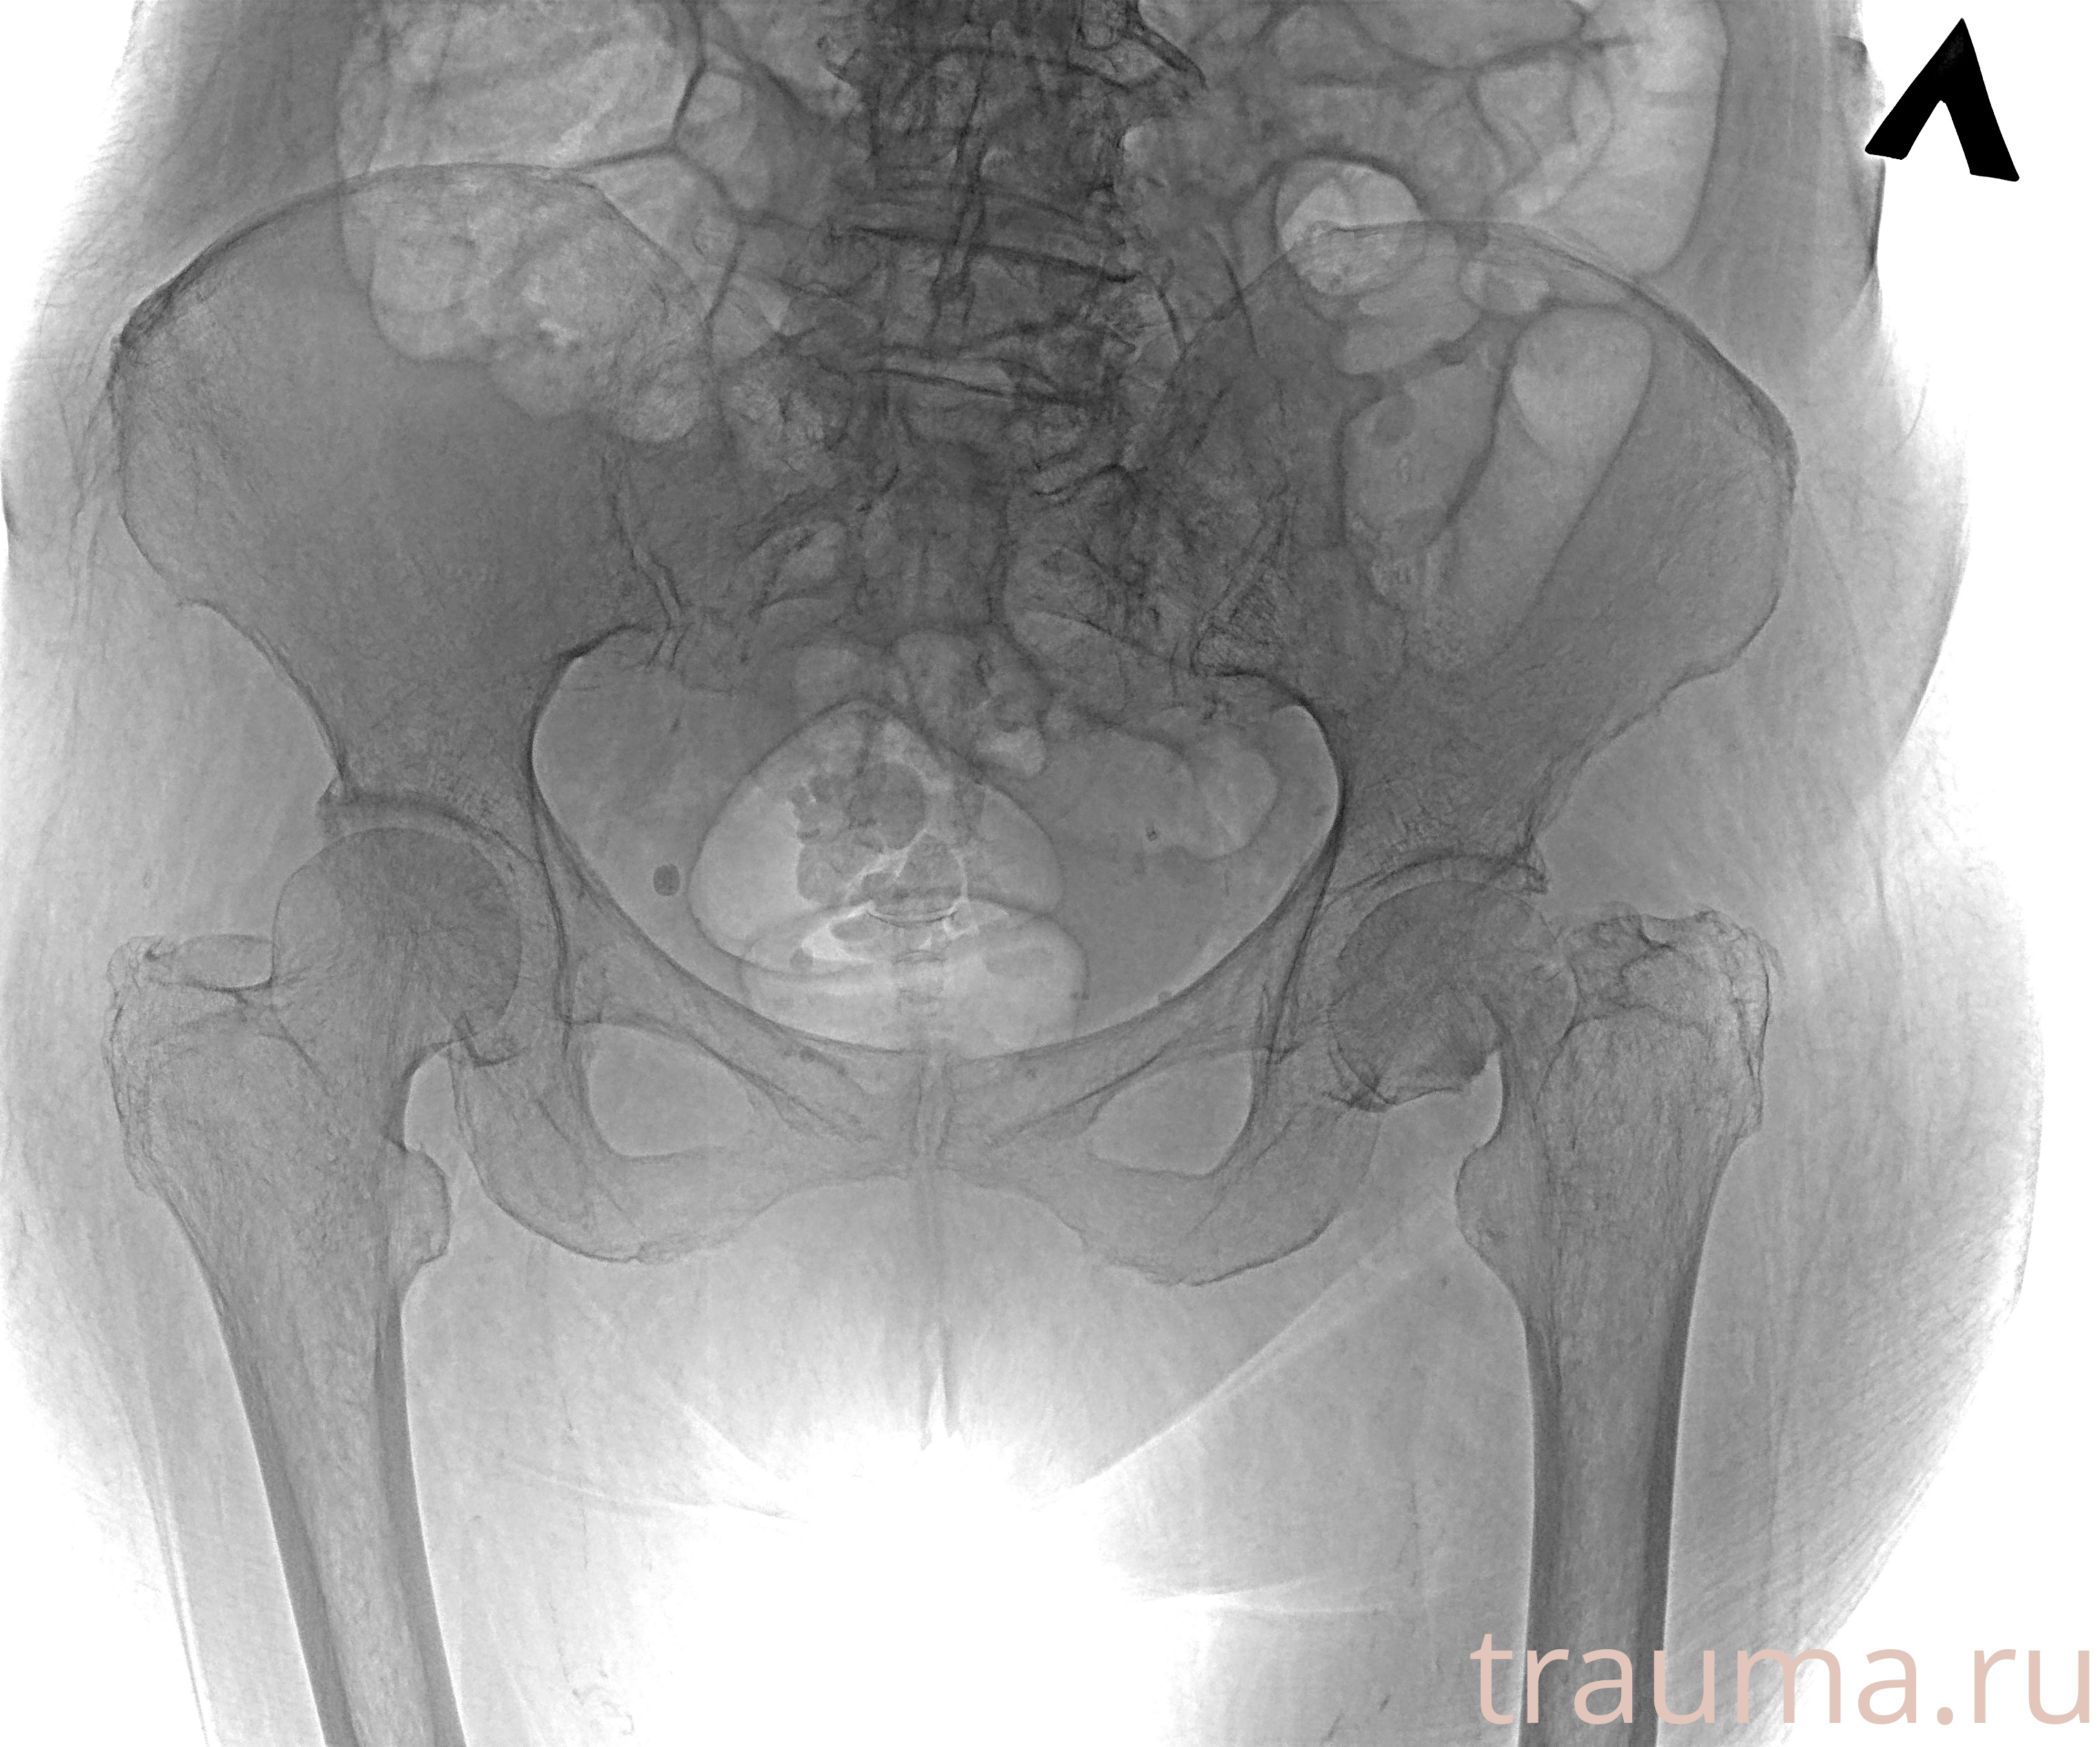

Рентгенограммы

Рентген на дому: по вашему адресу приезжает врач-рентгенолог, травматолог-ортопед с мобильным рентгеновским аппаратом, проводит диагностику травмы или заболевания, делает необходимые рентгенограммы, дает рекомендации по дальнейшему лечению. Получить качественные снимки в домашних условиях возможно благодаря уникальной методике, разработанной МосРентген Центром для института  Склифосовского